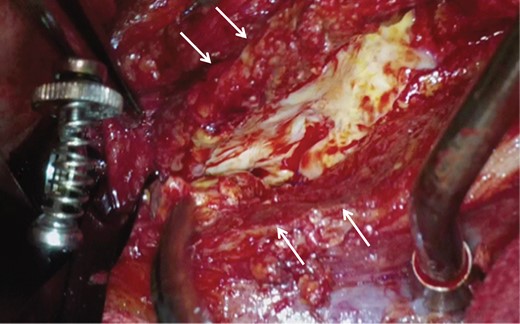

A midline laparotomy exposed the white-changed retroperitoneum. Adjacent organs, including the duodenum and the ileum, were adherent to the aneurysmal wall, but fibrotic change to the retroperitoneum was very limited. After proximal control to clamp suprarenal aorta and distal control to clamp bilateral common iliac artery were obtained in sites distant from the thickened parts of the juxtarenal AAA, the aneurysm was opened longitudinally. The anterior and lateral walls of the aneurysm were significantly thickened (Fig. 2). A Dacron bifurcated graft [Hemashield Gold 14 × 8 mm2, MAQUET Cardiovascular LLC, San Jose, CA, USA] was anastomosed proximally to the infrarenal aorta and distally to the bilateral common iliac artery. This operation was performed in 197 min without transfusion.

Intraoperative image showing that a small range of the aneurysmal wall was severely thickened (white arrows) but the fibrotic change of the retroperitoneum was limited.